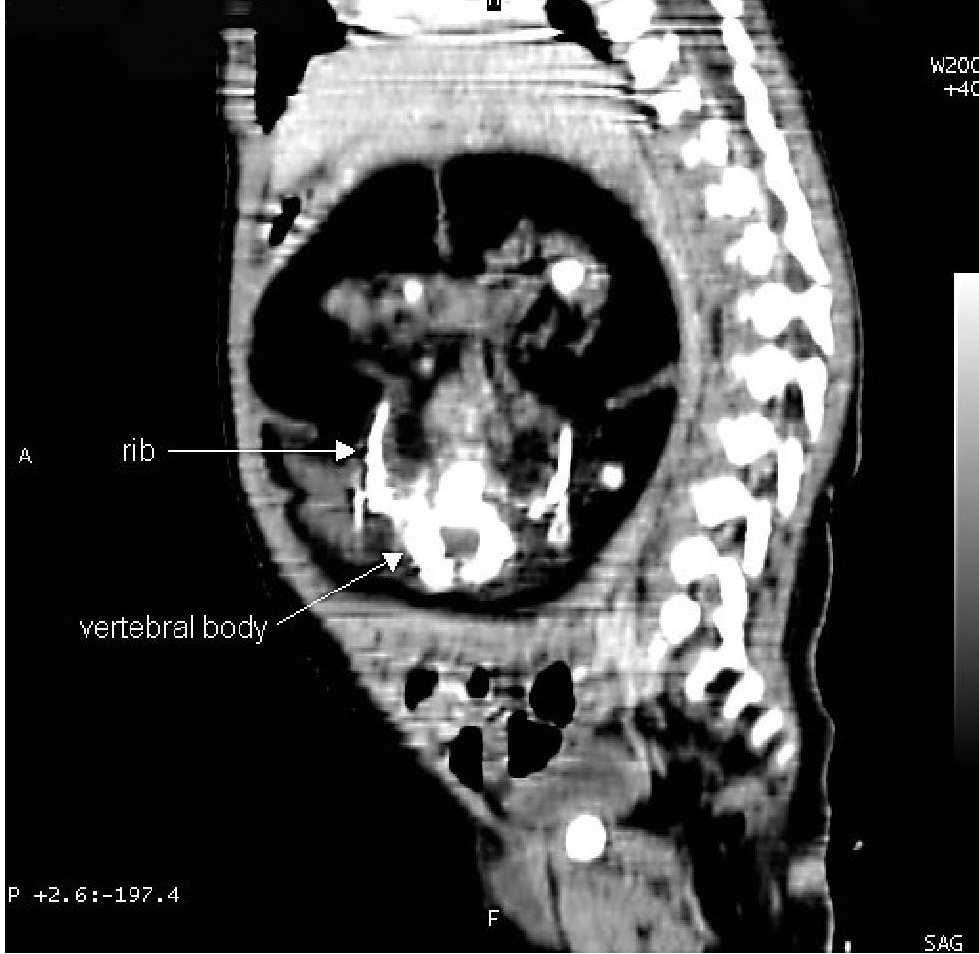

A firm abdominal mass was palpated at the right upper quadrant, hence, a CT Scan was requested. The scan reveals a huge complex intraabdominal mass with septations, calcifications, long bones and axial skeleton, highly considering Fetus in Fetu (Figure 1). After being cleared, the patient underwent exploratory laparotomy with incidental appendectomy and excision of FIF.

Figure 1. Computed tomography, sagittal view, depicting a huge, complex and septated intrabdominal mass with opacities representing the vertebral body and rib.

Our case fulfilled the diagnostic criteria of fetus in fetu on sonography and pathologic examination. On pre-operative CT scan, there was an anencephalic acardiac mass with identifiable ribs, extremities and spine within an intraabdominal cystic mass (Figure 1). Autopsy findings revealed a solid mass with immature upper extremities and spine inside a fluid-filled sac. Microscopic evaluation of the solid mass had the general tissue characteristics of Fetus in Fetu, with right optic placode, primitive gut, underdeveloped spinal cord and urethra.